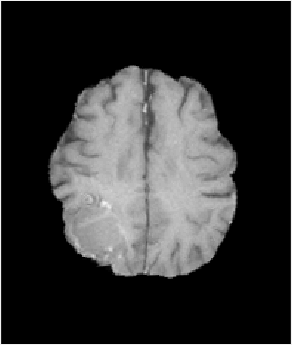

[Uncaptioned image] [Uncaptioned image] [Uncaptioned image] [Uncaptioned image]

[Uncaptioned image] [Uncaptioned image] [Uncaptioned image]

(a) (b) (c) (d)

Fig. 6: Example BRATS reconstructions: (a) tumor image; (b)-(d) reconstructions (top) and tumors (bottom); (b) PCA model w/o regularization; (c) PCA model w/ one and (d) w/ two regularization steps.

Fig. 6 shows decomposition results for our PCA models. We pick γ=5.0𝛾5.0\gamma=5.0 for the model without and γ=2.0𝛾2.0\gamma=2.0 for models with regularization. The goal is to allocate as much of the tumor as possible to the abnormal part, S𝑆S, while keeping the normal tissue in the quasi-normal part of the decomposition. Qualitatively, our models identify tumor/normal areas, while retaining image details in normal tissue areas.